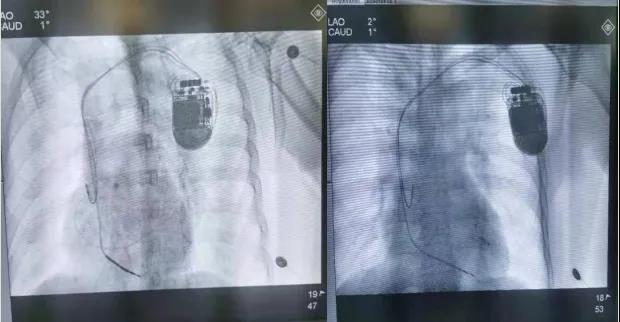

呼和浩特市第一医院心血管内科病例分享——CRT-D手术

患者,男,64岁,10年前因急性心肌梗死在外院行急诊PCI植入支架一枚,2021年7月出现胸憋、心悸,伴肩背部疼痛及咽喉部紧缩感,就诊于我院行心电图检查示室性心动过速,给予抗心律失常药物无效,电复律后恢复窦性心律。2021年11月11日再发室性心动过速于我院急诊科电复律转窦后转入我科。室性心动过速是心肌梗死后常见的恶性心律失常,极易发展成室扑、室颤,可危及生命,是心源性猝死的主要原因。鉴于患者反复出现恶性心律失常,猝死风险高,入院后科室高度重视,开展疑难危重病历讨论,并向侯煜院长及高江峰主任汇报患者病情。患者反复多次出现室性心动过速,且心彩超提示心脏扩大,左室射血分数明显降低,BNP明显升高,患者已出现明显心力衰竭表现,药物治疗效果差,心电图QRS波明显增宽,猝死风险极高,经过与患者及家属的多次沟通,经过综合分析及充分论证,决定为患者安装CRT-D,手术历时1小时40分钟,圆满成功。在既往CRT-D手术基础上,进一步改进和优化。本次手术使用先进的DF4除颤导线和Quartet左室四极导线,DF4除颤导线配合三合一除颤端口,将传统CRT-D的8颗螺丝减至3颗,缩短了手术时间,有效减小囊袋体积,降低感染风险,左室四极导线,可从10个向量测试左室起博阈值,增强恶性心律失常的识别,提升了CRT-D除颤及起博功能的有效性及安全性,有效降低患者猝死的风险。术后患者心电图QRS波宽度明显缩小,患者心衰症状明显改善,仅在患者胸部留有一处小切口,切口愈合良好,未出现切口感染。患者及家属对手术非常满意。